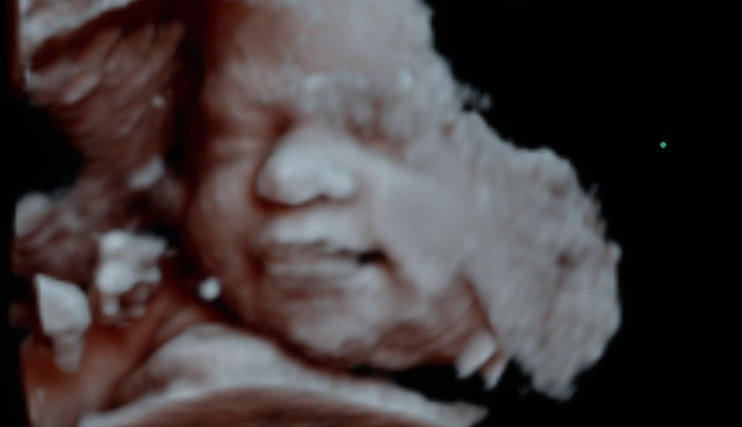

Ultrassom 3D e 4D

Este exame pode ser realizado em qualquer período da gestação, mas ele se torna interessante entre a 26ª e a 31ª semanas, quando o feto já está quase totalmente formado e podemos visualizar o rostinho do bebê.

O exame em 3D mostra detalhes do corpo do bebê, sendo possível ver o rosto e os órgãos genitais com mais nitidez, enquanto no exame em 4D, além das feições bem definidas, também é possível visualizar os movimentos do feto na barriga da mãe.